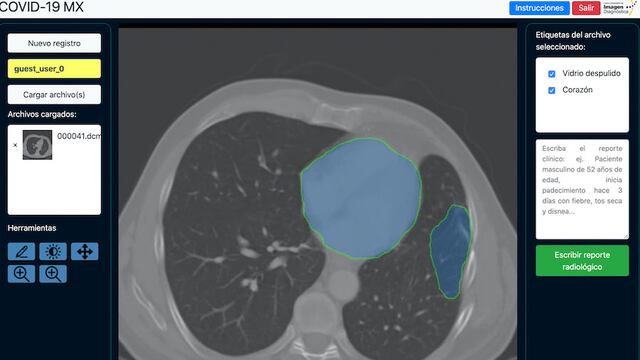

El algoritmo del programa determina con una radiografía de tórax de quién podría ver complicada su salud por Covid-19.

Fue así como el equipo nuevoleonés desarrolló la plataforma que contiene un algoritmo que se va nutriendo de radiografías de pacientes con neumonía, y ahora también con Covid-19.

Se dijo que este estudio se centra en los pacientes con sintomatología propia del Covid-19 y quienes potencialmente son más vulnerables de padecer complicaciones respiratorias, tanto con suministro de oxígeno o en su calidad de intubados.

El radiólogo Guillermo Elizondo explicó que en determinada situación, cuando estén monitoreando la respiración de algún paciente, la plataforma dará servicio para saber cuál de ellos pudiese complicar su estado durante los cuidados hospitalarios.

Las imágenes obtenidas apoyarían los resultados de PCR a dar un diagnóstico más preciso.